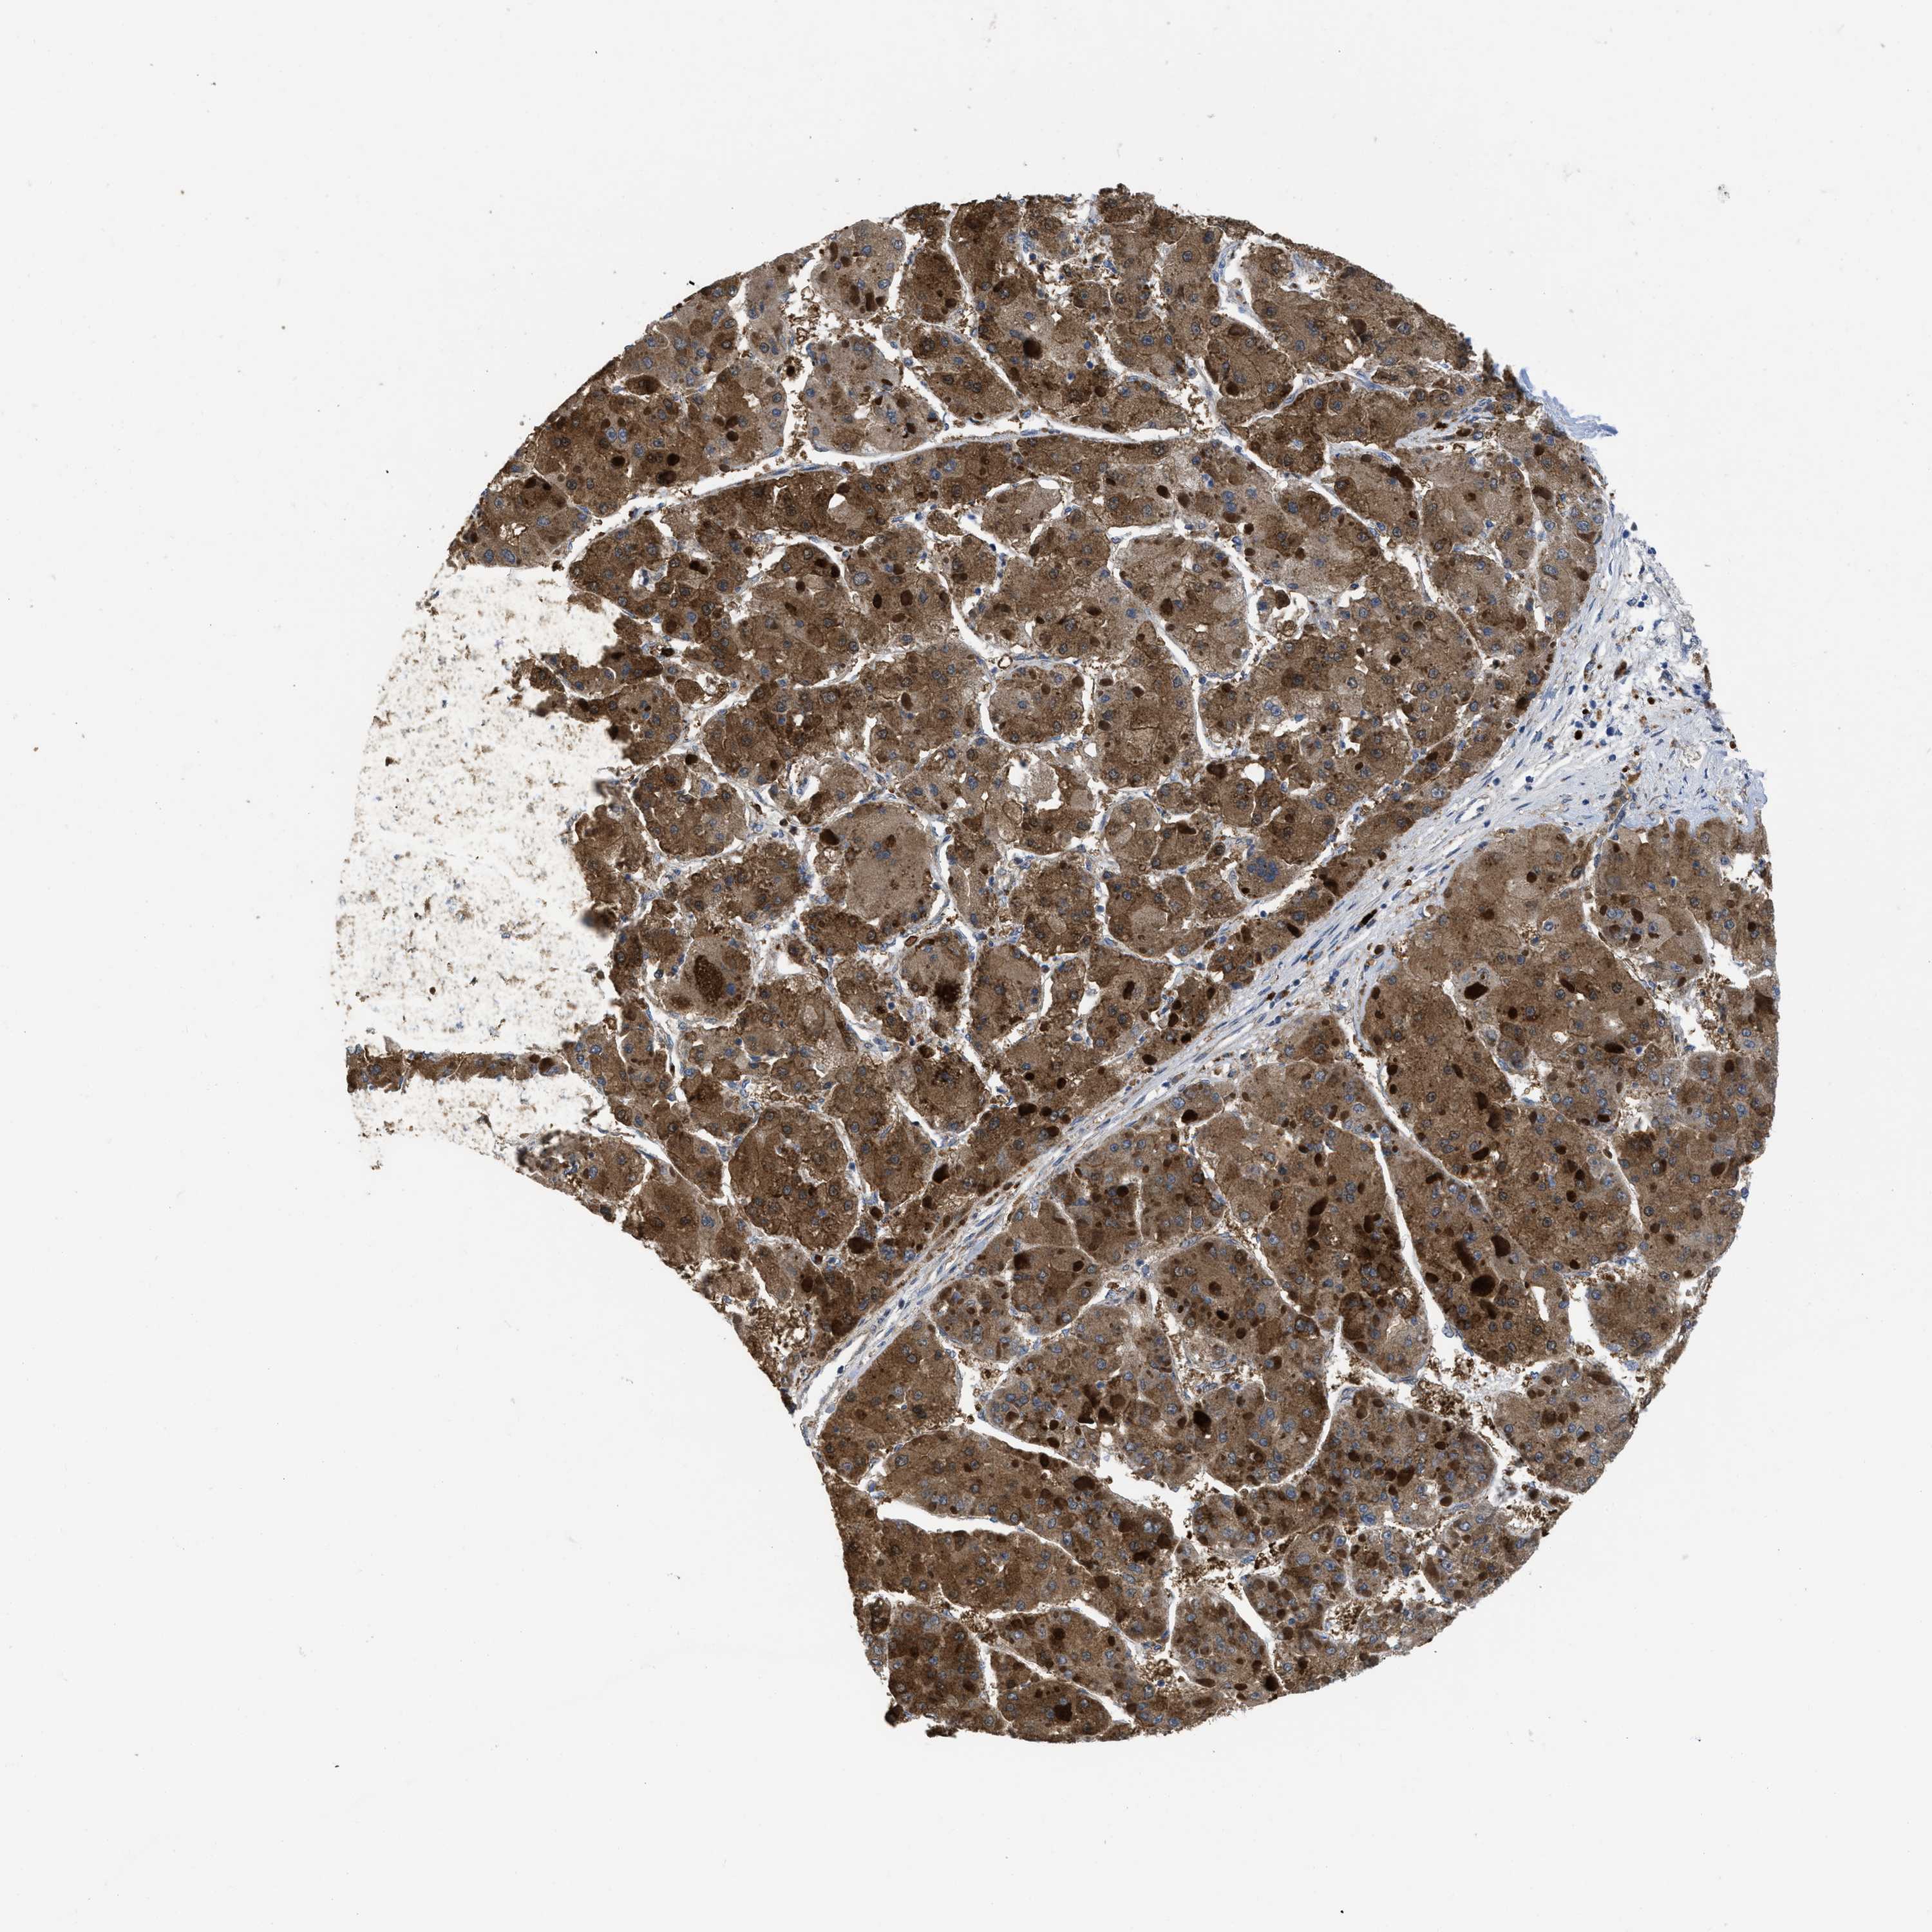

LIVER CANCER - Protein expressioni

A mouse-over function shows sample information and annotation data. Click on an image to view it in a full screen mode. Samples can be filtered based on level of antibody staining by selecting one or several of the following categories: high, medium, low and not detected. The assay and annotation is described here.

Note that samples used for immunohistochemistry by the Human Protein Atlas do not correspond to samples in the TCGA dataset.

Antibody stainingi

Antibody staining in the annotated cell types in the current human tissue is reported as not detected, low, medium, or high, based on conventional immunohistochemistry profiling in selected tissues. This score is based on the combination of the staining intensity and fraction of stained cells.

Each image is clickable and will lead to virtual microscopy that enables deeper exploration of all samples and also displays staining intensity scores, fraction scores and subcellular localization as well as patient and tissue information for each sample.

Antibody HPA043236

Antibody CAB018600

Staining

High

Medium

Low

Not detected

Intensity

Strong

Moderate

Weak

Negative

Quantity

>75%

75%-25%

<25%

None

Location

Nuclear

Cytoplasmic/membranous

Cytoplasmic/membranous,nuclear

Cholangiocarcinoma

Carcinoma, Hepatocellular, NOS